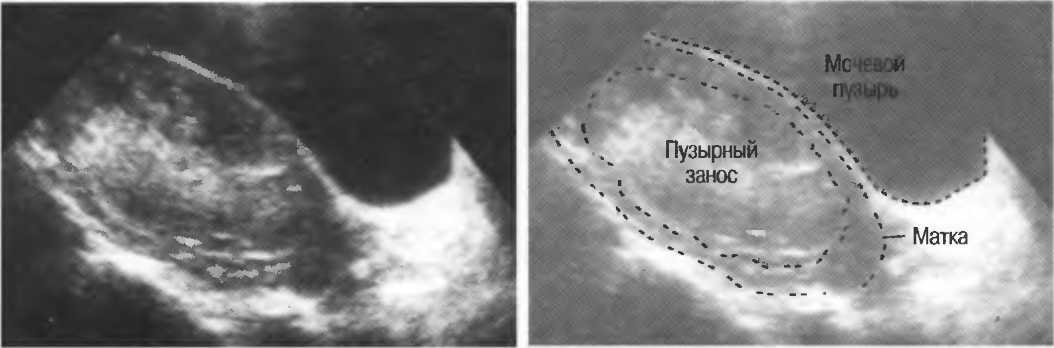

Медицина и диагностика: Инвазивный пузырный занос на УЗИ